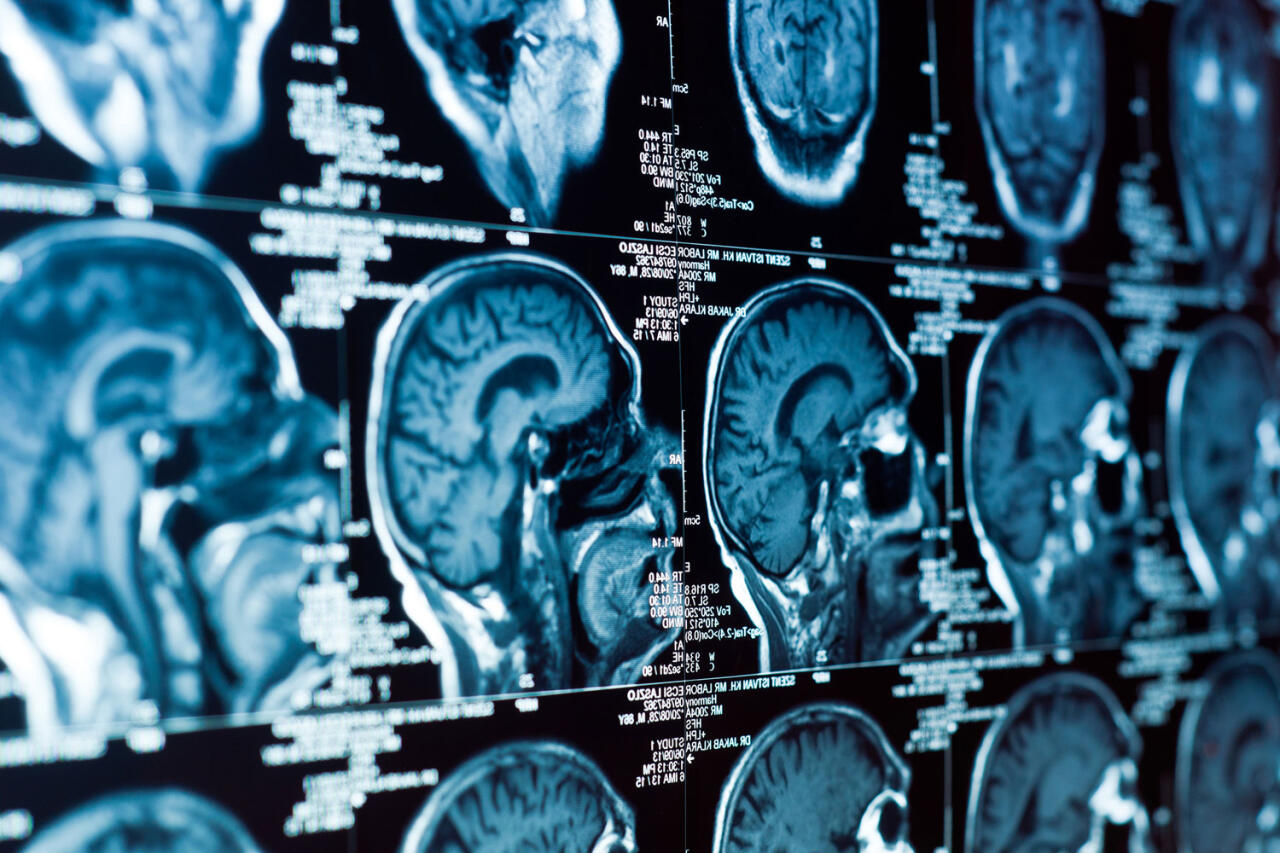

ИИ научили различать типы опухолей мозга во время операции

Ученые из Гарвардской медицинской школы разработали инструмент на базе искусственного интеллекта, который способен с высокой точностью различать два типа опухолей головного мозга: глиобластому и первичную лимфому центральной нервной системы (ПЛЦНС). Результаты исследования опубликованы в журнале Nature Communications (NatCom), передает Day.Az со ссылкой на Gazeta.ru.

Новая система получила название PICTURE (Pathology Image Characterization Tool with Uncertainty-aware Rapid Evaluations). Тесты показали, что модель работает с почти идеальной точностью - свыше 98% - даже в сложных условиях интраоперационной диагностики. Этот метод медицинского обследования применяется непосредственно во время хирургического вмешательства.

Во время операций нейрохирурги часто используют так называемые замороженные срезы опухоли для быстрой оценки. Однако из-за изменений клеточной структуры при заморозке и визуального сходства между типами рака возможны диагностические ошибки.